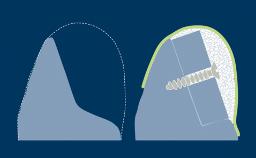

On the basis that implants should always be placed in an ideal three-dimensional prosthodontic position, peri-implant defects in the bone and soft tissues are often encountered when implants are placed. If these defects are minor, they can be treated at the time of implant placement with a high degree of predictability.

If the defects are large, a staged approach, in which the augmentation is performed first and the implant placed at a later time, is preferred.